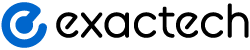

Clinical uses for PRP are many and continue to be investigated. It has been used to treat tendinopathies, partial tendon tears, complete tendon tears, arthritis, and as a surgical adjunct to aid wound healing, tendon healing and reduce pain.

Choosing the right PRP system plays a critical role in the success of your treatments. While there is no clear consensus on the best preparation, it is becoming clear that LR or LP PRP may be better in certain indications. LR-PRP may be beneficial where a strong inflammatory response is desired, such as chronic tendinopathies. LP PRP seems to be more beneficial in treating the symptoms of osteoarthritis and may help the healing of the rotator cuff tendon after surgery. A system that enables the surgeon to choose the right formulation for the right patient puts you in the best position to help.